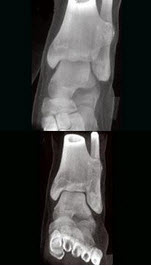

195、单项选择题

男,13岁,右跟骨疼痛不适3周,右跟骨侧、轴位摄片如图示,最可能的诊断是()

A.右跟骨结核

B.右跟骨骨囊肿

C.右跟骨骨巨细胞瘤

D.右跟骨血管瘤

E.以上均不正确